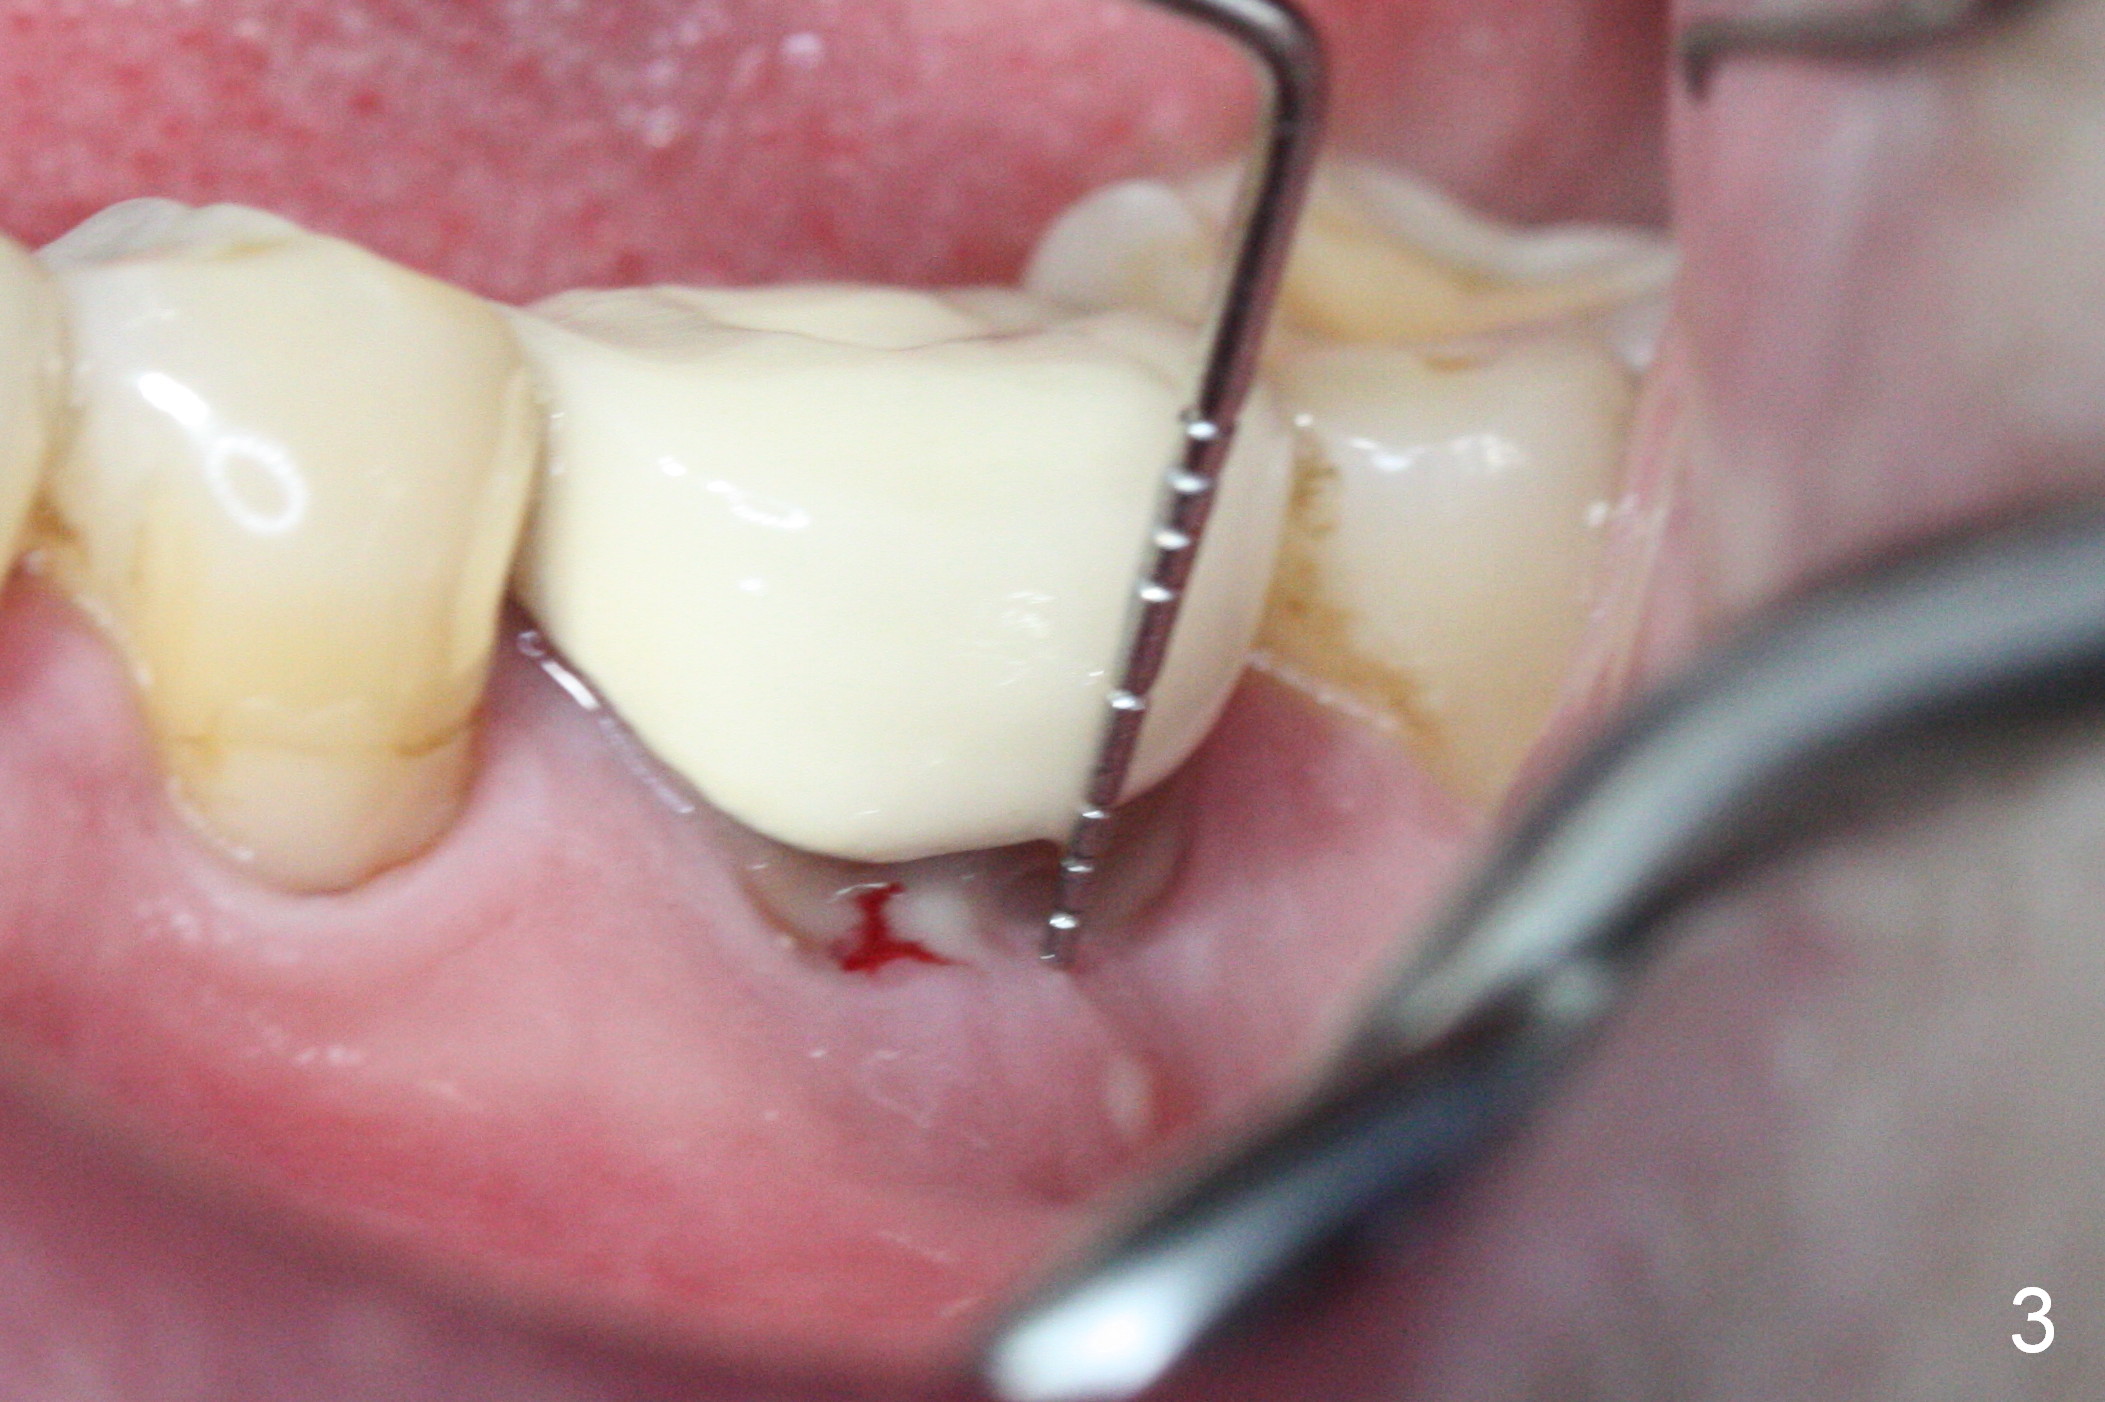

The asymptomatic tooth (#19) has a midbuccal fistula (Fig.1 <). The mesiobuccal pocket is 10 mm with purulent discharge from the sulcus (Fig.2,3). The mesiobuccal wall defect is confirmed when the tooth is extracted. Osteotomy is initiated lingually in the septum following septal crestoplasty (flattening) (Fig.4: using 1.6 mm drill for 9 mm). Since the lingual portion of the osteotomy is higher, it is difficult to use drill with stopper. For the narrow septum osteotomy, multiple drills are used sequentially (Fig.5 after 4.3 mm drill). A 4.5x11 mm dummy implant is placed (Fig.6) apparently too deep. When a 5x11 mm IBS implant is being placed, the depth is tightly controlled (Fig.7). The implant is apical to the lingual crest, whereas there is ~ 2 mm implant exposure buccally. That is, there is a large gap mesiobuccally (Fig.8), which is filled with .5-1.5 mm allograft (Fig.9 *). A 6.5x5.7(3) mm abutment (A) is placed and trimmed for an immediate provisional (Fig.10 P). The lacerated buccal gingiva is sutured as well as application of Perio Glue.